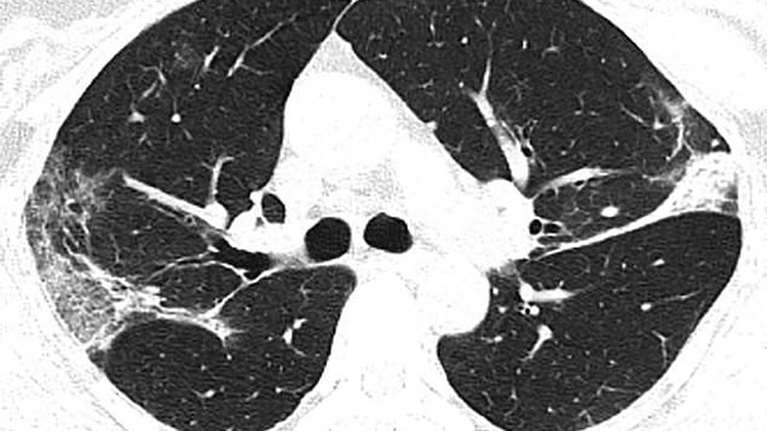

Κορονοϊός: Δείτε τι συνέβη στους πνεύμονες Κινέζου ασθενούς που νόσησε και πέθανε

Οι άτυχοι ασθενείς ήταν στην Κίνα όταν ξέσπασε η επιδημία.